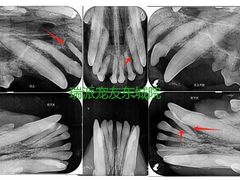

• 东莞宠友24H宠物中心医院·转诊夜诊·异宠(新河北路院)

美食鉴赏家 | 24-04-08

报错

• -东莞宠友24H宠物中心医院·转诊夜诊·异宠(新河北路院)